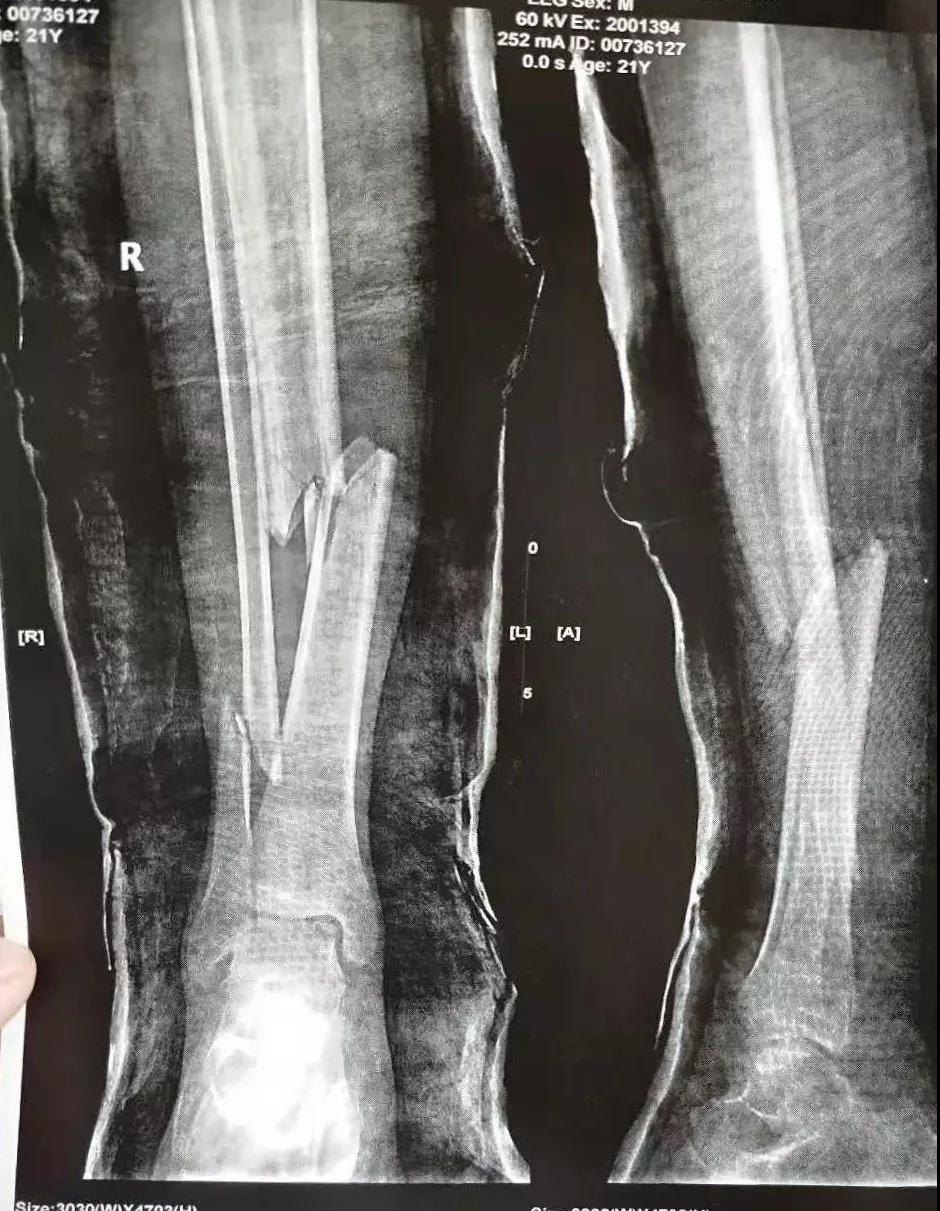

这名21岁的男性患者一个月前因车祸致伤,在当地某三甲医院确诊为右胫腓骨粉碎性骨折,骨折移位明显,建议手术治疗,因既往患严重慢性再生障碍性贫血病史16年,一般状况差,需长期输注血液制品维持三系细胞水平,麻醉及手术风险极高。虽经当地积极内科治疗,患者一般状况仍差,无法耐受手术治疗。患者及家属经多方打听,抱着最后一丝希望来到我院骨二科求治。

骨二科张延平主任接诊后经仔细询问病史,详细阅读近期X线、CT等病历资料,认为患者骨折移位明显,目前骨折无任何愈合迹象,若保守治疗,骨折将无法愈合,后期不能下地活动,严重影响患者生活质量。同时患者合并慢性再障,血常规结果各项指标均极低,围术期发生麻醉意外、大出血、感染等风险极高;而我院作为西安市级最大的三甲综合医院,综合实力深厚,既往相关疾病治疗经验丰富,多次通过多学科诊治为合并复杂内科疾病患者保驾护航,为患者创造手术时机,提高患者生活质量,遂将患者收住院。住院后,立即成立了由张延平主任、杨寅副主任、山卉护士长、梁晨主治医师、刘邦定主治医师、李鑫护师组成的手术治疗小组。经初步检查,患者血常规结果较当地检验结果更差,三系细胞均极低,其中血小板仅为1(正常值为100-300),血红蛋白55g/L。遂立即请血研所李罡灿主任医师会诊,给予升高白细胞、纠正贫血、升高血小板等治疗,经积极治疗患者血常规各项指标均较入院时改善。张延平主任再次组织由血研所李罡灿主任医师、麻醉科崔晓岗主任、感染科付建军主任、药剂科韩小年副主任药师等参加的术前讨论。讨论后一致认为患者目前各项指标虽然较入院时改善,但因其慢性再障病史长,骨髓造血及储备能力极差,围术期发生大出血、伤口感染甚至全身感染等风险仍极高,术中及术后需准备大量血小板防止大出血,同时需高度警惕手术切口、取骨区术后发生感染。为尽快为患者施行手术,治疗小组积极联系输血科为患者备血,并为患者制定了围术期抗感染方案;在我院输血科存血量严重不足的状态时,输血科张养民主任亲自联系市中心血站为患者准备手术中及术后所需的血小板制品。手术小组为患者制定了周密的手术方案及风险预案,10月31日,在麻醉科王永宏副主任医师、手术室高洁、赵耀护师的配合下,为患者施行了右胫骨粉碎性骨折切开复位、髂骨取骨植骨内固定术,手术历时70分钟,安全返回病房。术后患者渗血多,1周内连续每日平均渗血超过100ml,并出现发烧,最高39℃,复查血常规三系细胞较术前再次明显降低。李罡灿主任医师、付建军主任、韩小年副主任药师多次来科会诊,及时调整患者的治疗方案,输血科再次为患者的救治提供了强有力的支援和保障。在山卉护士长带领的护理团队精心护理下,患者未发生压疮等卧床并发症。目前该患者术后恢复良好,已出院进行下一步康复治疗。